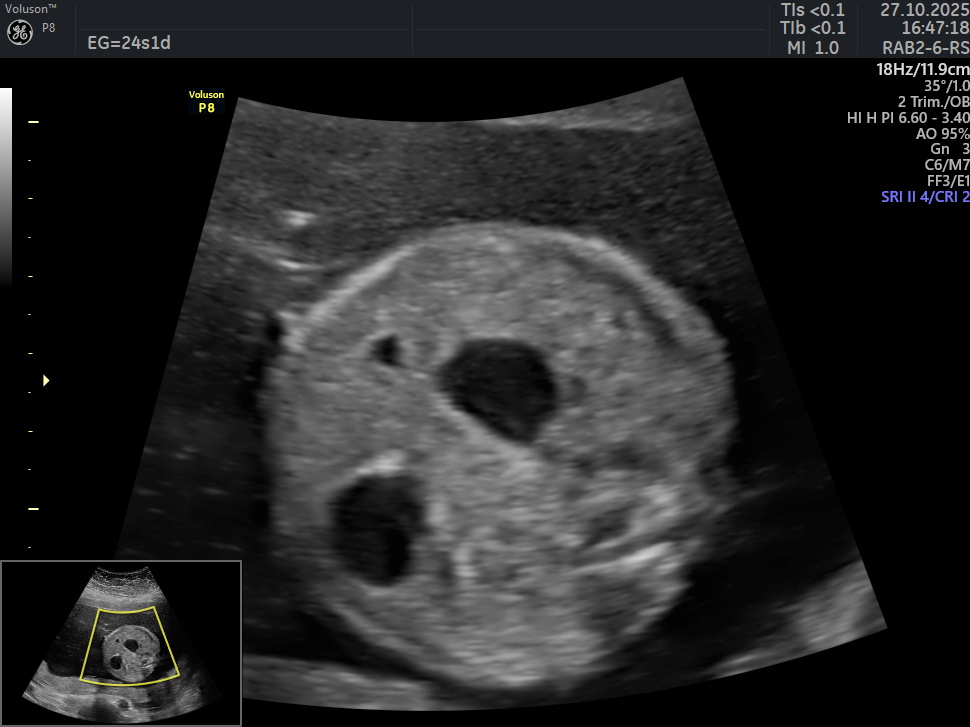

# 96 - Signo de la doble burbuja

Se presenta el caso de una paciente de 39 años de edad, primigesta, sin antecedentes personales ni familiares de relevancia. La paciente adjunta el estudio de screening de aneuploidías de la semana 11-14, que arroja bajo riesgo. Las imágenes que se presentan a continuación corresponden al estudio morfológico fetal realizado en la semana 24. Seleccione la opción correcta : A. Se visualiza cámara gástrica dilatada, conectada con una imagen quística anecogénica, de probable origen duodenal (Signo de la doble burbuja). B. La anatomía es de apariencia normal para la edad gestacional. C. Los hallazgos podrían corresponder a una probable atresia esofágica. D. Los hallazgos podrían corresponder a una dilatación quística del conducto biliar.

Respuesta correcta: A. Se visualiza cámara gástrica dilatada, conectada con una imagen quística anecogénica, de probable origen duodenal (Signo de la doble burbuja).